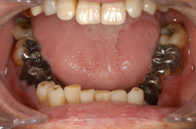

銀歯が錆びて黒くなってます

以前に保険で治療した際に銀の詰め物、かぶせ物を入れたんだけど、そこの銀歯が気になってしまう。気になりだすと鏡を見ても、写真を見ても、自分の目が銀歯に行ってしまう。

銀歯は審美面、健康面でオススメできません

先程も申し上げたように、いわゆる銀歯といわれる金銀パラジウム合金は保険制度の経済的な理由から選択された素材です。良いところは保険が効くので「安い」ということだけです。

審美的に見ると、銀歯は全く自然でないのでオススメできません。

それは奥歯の詰め物であってもです。